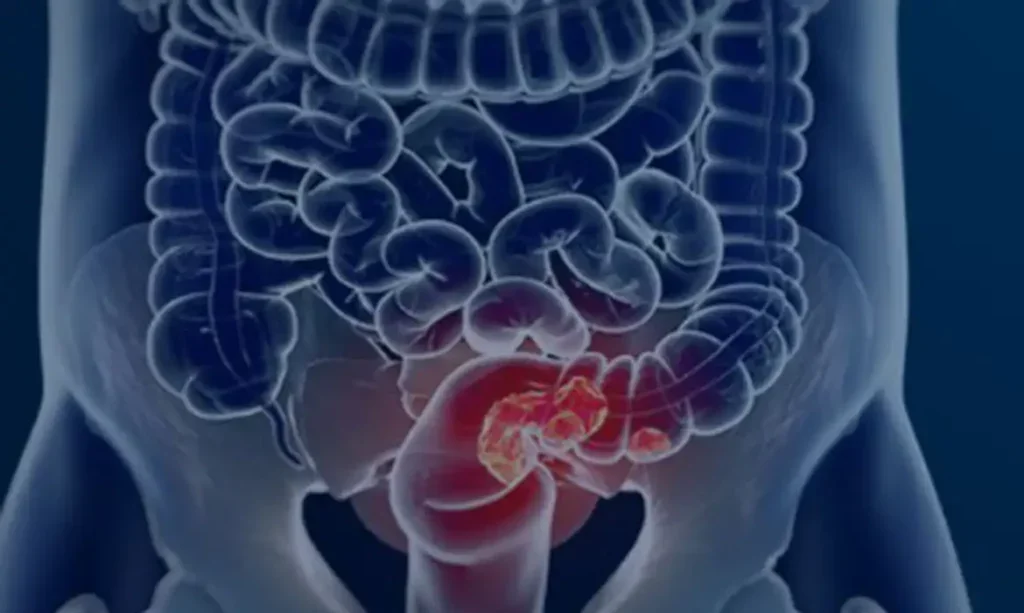

Um levantamento divulgado nesta quinta-feira (27), Dia Nacional de Combate ao Câncer, indica que mais de 60% dos pacientes com câncer colorretal no Brasil recebem o diagnóstico em estágios avançados. O estudo “Câncer colorretal no Brasil – O desafio invisível do diagnóstico”, da Fundação do Câncer, avaliou 177 mil casos registrados em hospitais públicos e privados entre 2013 e 2022.

Os dados mostram que o avanço da doença antes da identificação reduz significativamente as chances de tratamento efetivo.

“Se analisarmos o país como um todo, os dados mostram que 50% das pessoas chegam no estágio já metastático, estágio 4, e mais 25% no estágio 3. Somando os estágios, são mais de 70%”, disse.